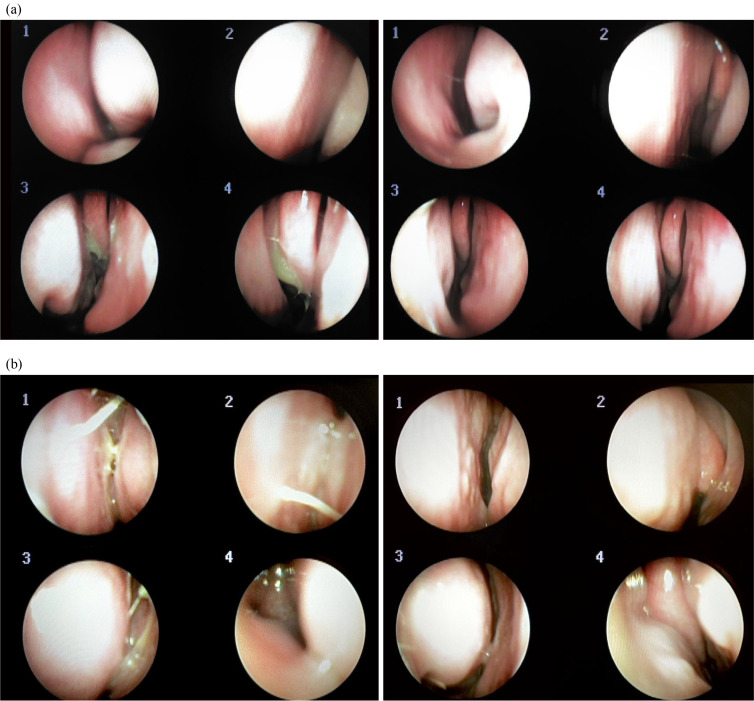

过敏性鼻炎(Allergic rhinitis, AR)和慢性鼻窦炎(chronic rhinosinusitis, CRS)是常见的上呼吸道疾病,经常共存。这些疾病虽然不会危及生命,但会显著降低生活质量,因其慢性和复发性而造成严重的社会经济负担,并对心理健康产生负面影响。在某些情况下,AR和CRS与包括自杀倾向在内的严重后果有关。本报告报告了两例年龄分别为42岁和37岁的女性,她们经历了反复发作的AR和CRS症状,如持续的鼻塞、鼻漏,导致吃饭时谈话困难和睡眠障碍,尽管接受了常规治疗,但持续了20多年。两例患者均接受8-12周的治疗方案,包括小天龙汤(SCRT)和针对蝶腭神经节(SPG)的超声引导针灸。采用鼻内窥镜检查结果、鼻结膜炎生活质量问卷评分和鼻总症状评分来评估治疗效果。观察到显著的治疗后改善,并且这些效果在停止治疗后持续了3个月,没有明显的不良事件报告。虽然鼻内皮质类固醇是AR和CRS的标准治疗方法,但大约30%的患者要么症状缓解不足,要么因不良反应而停止使用,这往往导致症状复发。相比之下,SCRT和spg靶向超声引导针灸联合治疗可能是一种有希望的替代治疗选择,显示出持续的症状改善而没有明显的不良反应。

Allergic rhinitis (AR) and chronic rhinosinusitis (CRS) are common upper respiratory tract diseases that frequently coexist. While not life-threatening, these conditions significantly diminish quality of life, impose substantial socioeconomic burdens due to their chronic and recurrent nature, and negatively impact mental health. In some cases, AR and CRS have been associated with severe outcomes, including suicidal tendencies. This report presents two cases of women aged 42 and 37 years who experienced recurrent AR and CRS symptoms, such as persistent nasal congestion, rhinorrhea, which led to difficulties in conversation during meals and sleep disturbances, for over 20 years, despite undergoing conventional treatments. Both patients received an 8-12 week treatment regimen consisting of Socheongryong-tang (SCRT) and ultrasound-guided acupuncture targeting the sphenopalatine ganglion (SPG). Treatment efficacy was assessed using nasal endoscopic findings, Rhinoconjunctivitis Quality of Life Questionnaire scores, and Total Nasal Symptom Scores. Significant post-treatment improvements were observed, and these effects persisted for 3 months after treatment cessation, with no significant adverse events reported. While Intranasal corticosteroids are the standard treatment for AR and CRS, approximately 30% of patients either experience insufficient symptom relief or discontinue their use due to adverse effects, often leading to symptom relapse. In contrast, the combination of SCRT and SPG-targeted ultrasound-guided acupuncture may offer a promising alternative treatment option, demonstrating sustained symptom improvement without significant adverse effects.